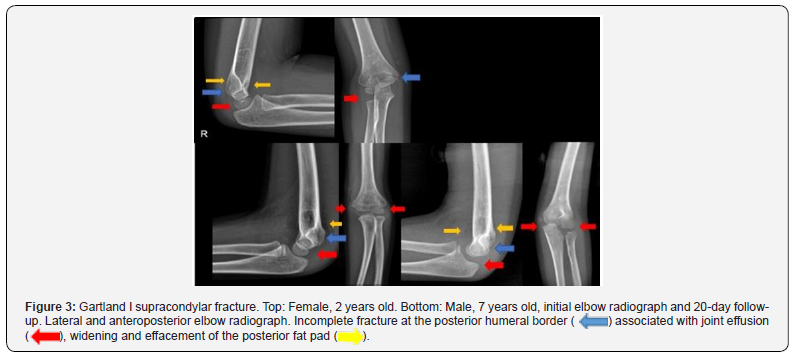

Upper extremity injuries are estimated to account for 65% of all fractures in children. The modified Gartland classification system for supracondylar fractures includes non-displaced type I, where the fracture line or fat pad sign is seen on the lateral radiograph (Figure 3) [5-8]. Gartland I supracondylar fracture. Top: Female, 2 years old. Bottom: Male, 7 years old, initial elbow radiograph and 20-day follow-up. Lateral and anteroposterior elbow radiograph. Incomplete fracture at the posterior humeral border ( ) associated with joint effusion (

) associated with joint effusion ( ), widening and effacement of the posterior fat pad (

), widening and effacement of the posterior fat pad ( ). Type II shows moderate displacement, where the posterior cortex remains in continuity (IIa without rotation, IIb rotation). (Figure 4) [2,3,8]. Type III shows complete displacement (Figure 5) and type IV is unstable in flexion/extension (intraoperative evaluation). Elbow radiograph, lateral and anteroposterior projection. Posteriorly displaced Gartland III supracondylar fracture (